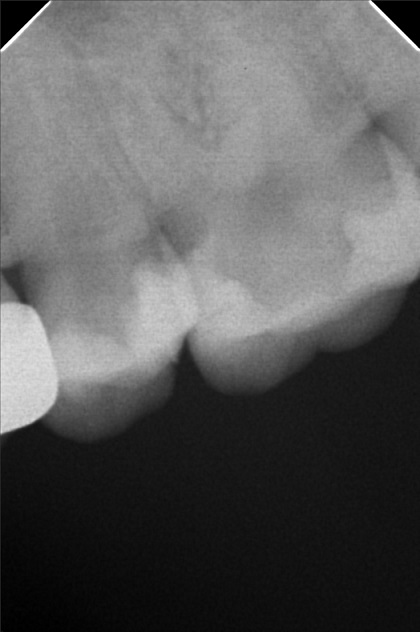

Edit Record Check our patient data records. Add patient information Patient Info Profile picture Last Name First Name Middle Name Birthdate Age Street Barangay City Country Zip Code Contact number Email Procedure 10/13/21- 26 LC with MTA MOD 23 Lingual Distal 11/24/21 - 25/27 LC# 27 #15 IRM -/Xray 03/16/22- zircinia prep on 15/16 shade: a3 body, cervical b3 digital impression done temporary crown done LC mesial 15, distal 14 xray on 24 3/25/22- installation 15, 16 zirconia opening of canal 24 TF with EUgenol 03/30/22 Lingual 18/ Buccal 19 Formocresol Incision and drainage Laser rx: co amoxiclav 625 mg/ mefenamic 500 mg 04/29/22- lingual 16.5mm buccal 19mm 05/04/22- obturation/ LC 8/12/22 - tooth prep #24 8/18/22- Cementation zirconia crown #24 8/26/22 - xray, intraoral radiograph 05/12/23- OP(L) 05/19/23- Xray/ Ozone/Resto - #21(mesial & lingual) 09/10/24 OP w/ air polisher 07/19/25 op with air polisher + fluoride 03/18/26 OP 04/08/26 #48 - Occ mesial MTA Fiber Biomimetic File delprado26.jpg File 2 delprado23-24-25.jpg File 3 6afb059c-2de8-4dc8-ac4d-ae6435b6dabc.jpeg File 4 katherine_del_prado.jpg File 5 katherine_del_prado_02.jpg File 6 katherine_del_prado_03.jpg File 7 File 8 File 9 File 10 File 11 File 12 File 13 File 14 File 15 File 16 File 17 File 18 File 19 File 20 Retain Record Retain Record Yes No Save Your Changes